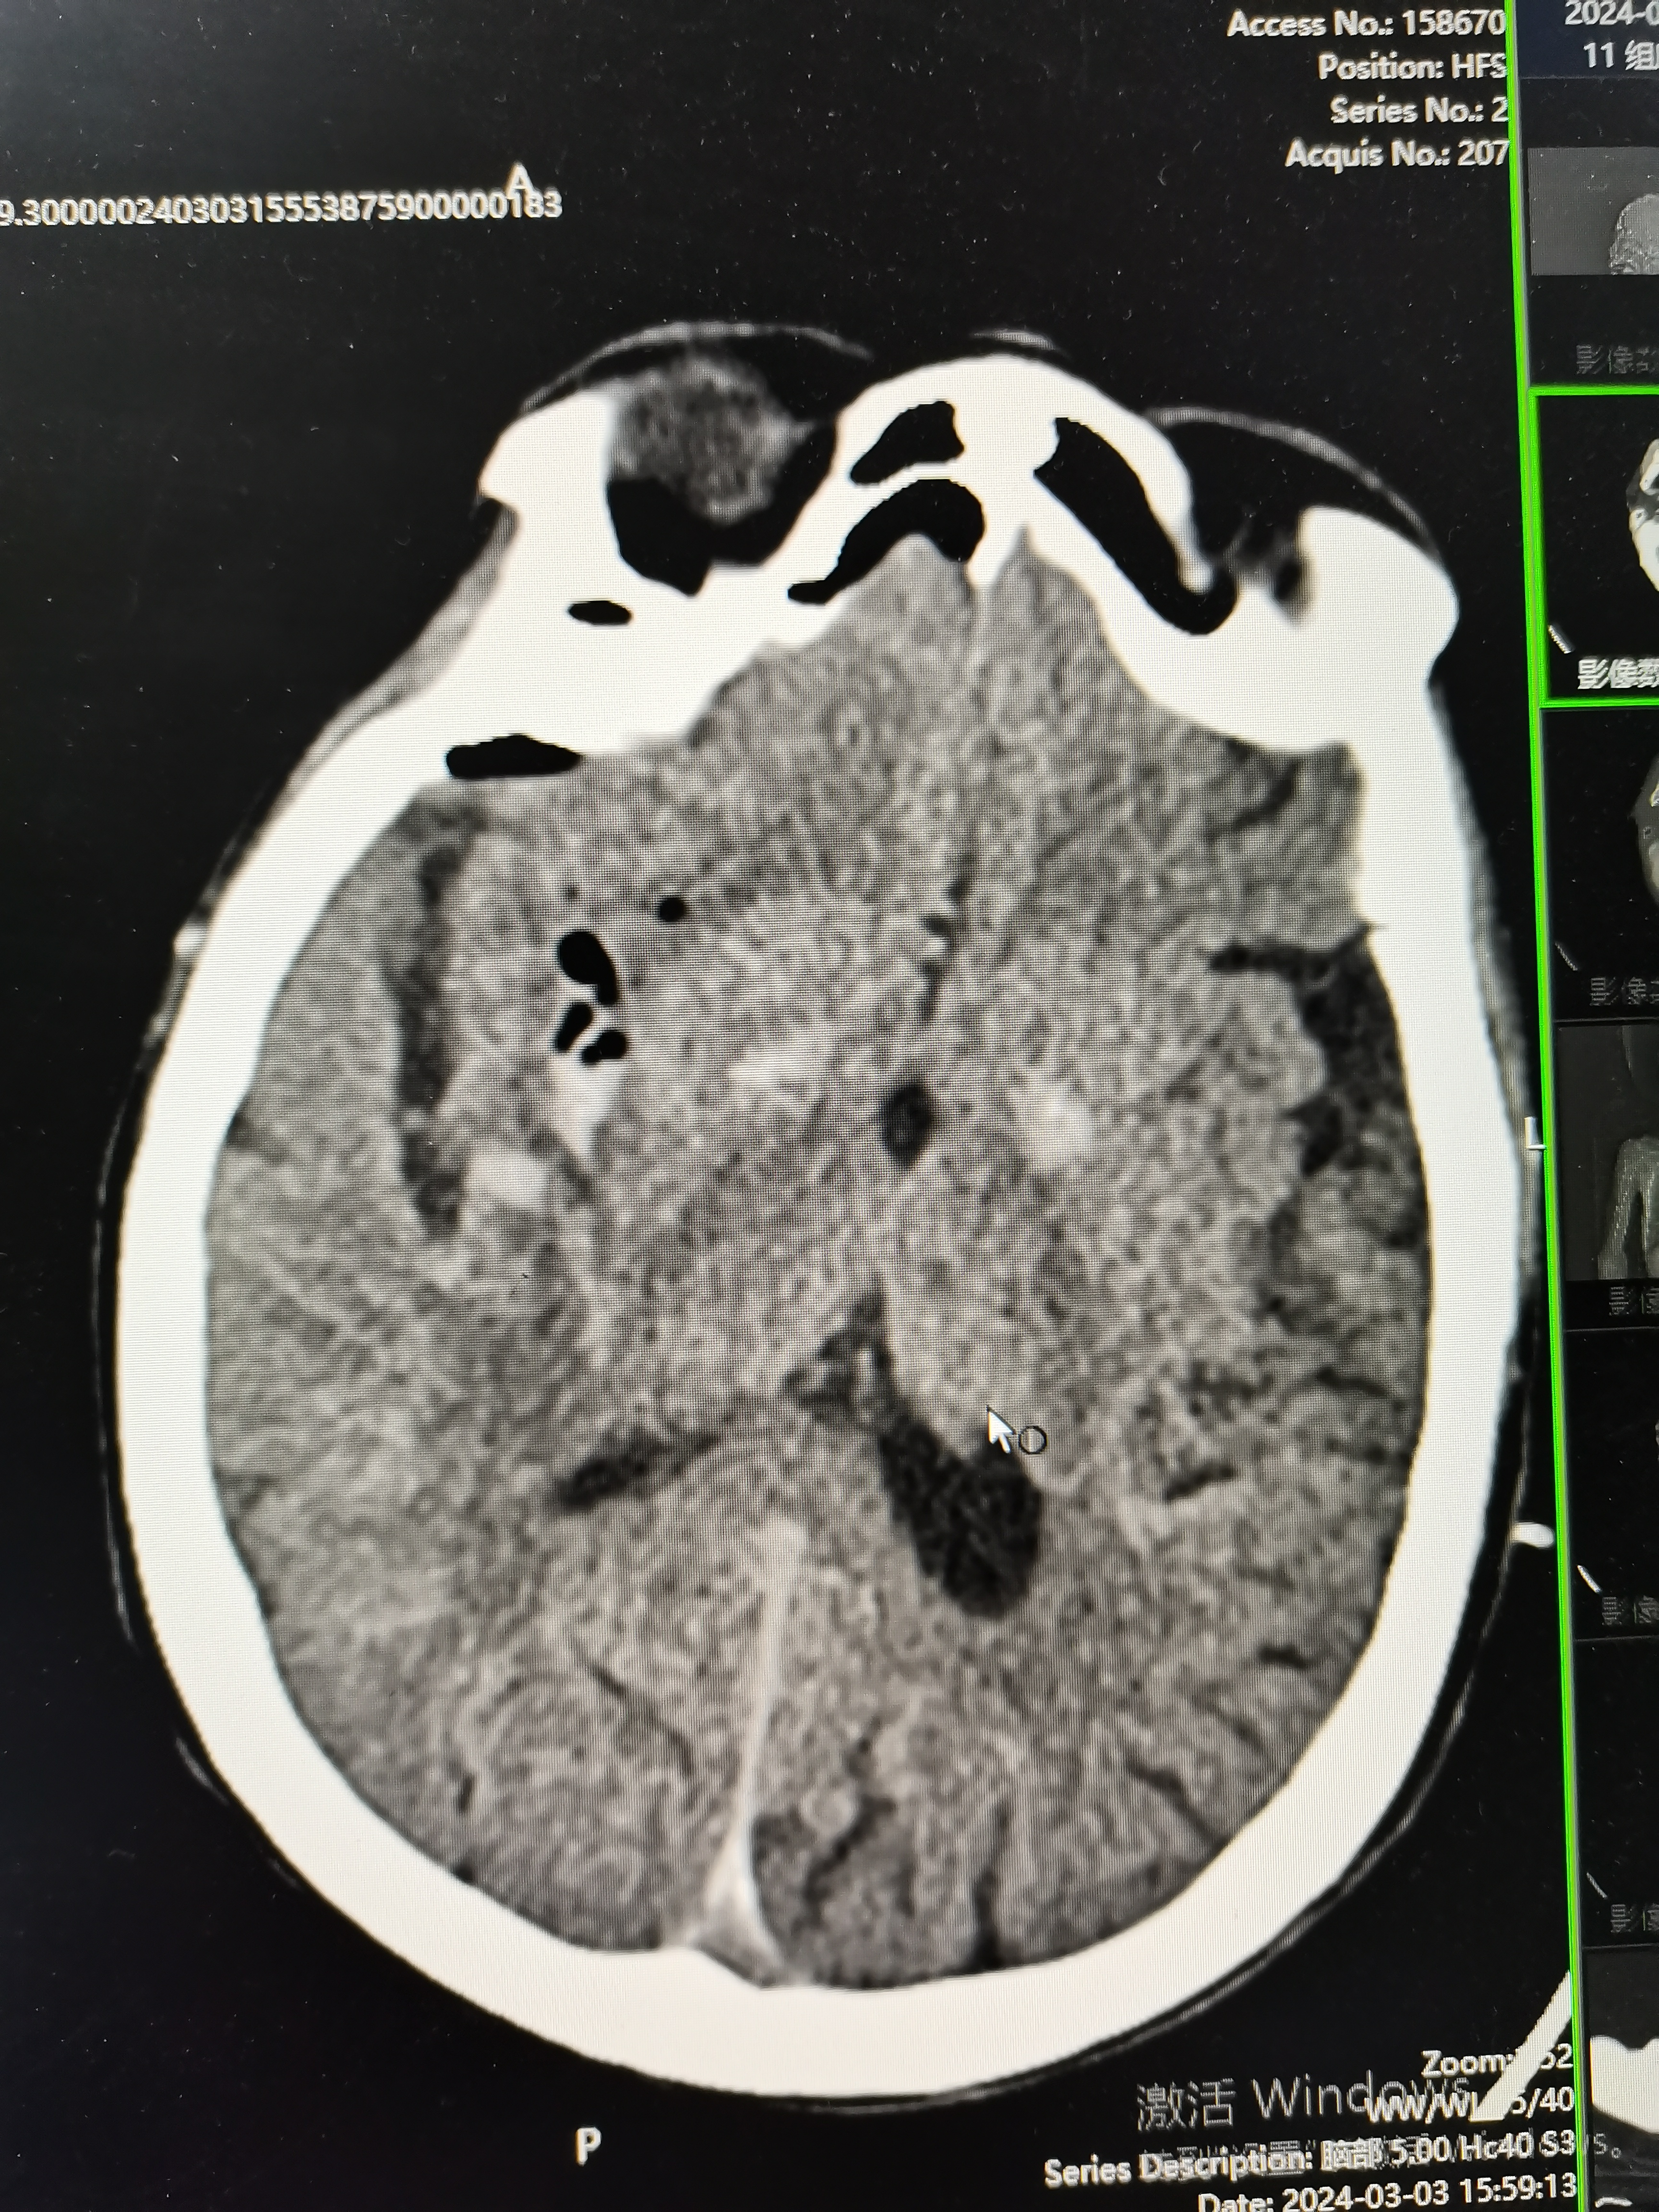

患者为77岁女性,有高血压等基础疾病,发病5小时余入院,术前片子如图

术前片子